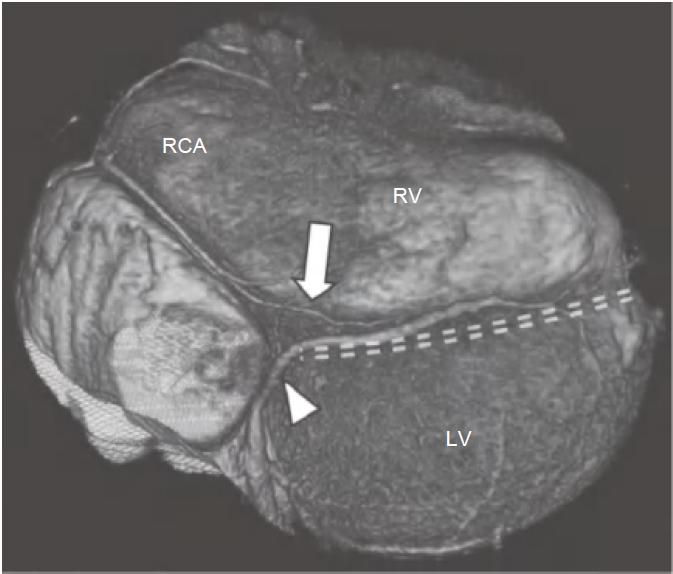

通常,RCA自右冠窦前方发出后在右房室间沟(RAVG)内向前然后向下走行,到达心脏的后方(图13-3及图13-4)。

图13-3 RCA(白箭)起自主动脉的前部,并沿RAVG(黑箭)走行。图中还可见位于前室间沟内(箭头)的LAD

AO.主动脉;PA.肺动脉;RA.右心房;RV.右心室;LV.左心室